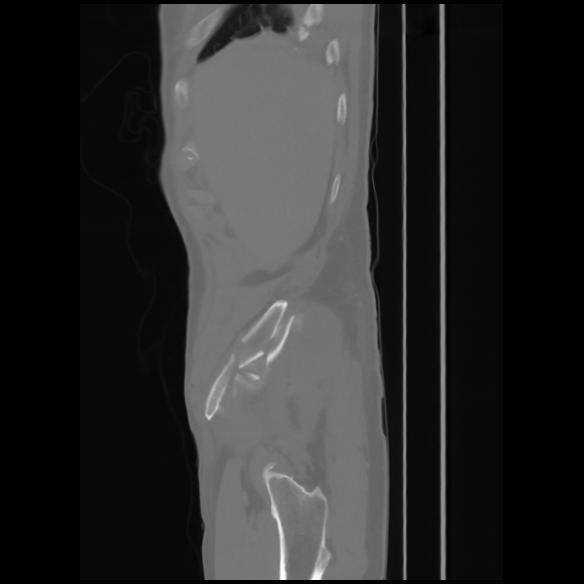

7 CUERPO,CE,Sagittal,3.000,CUERPO,Sagittal,